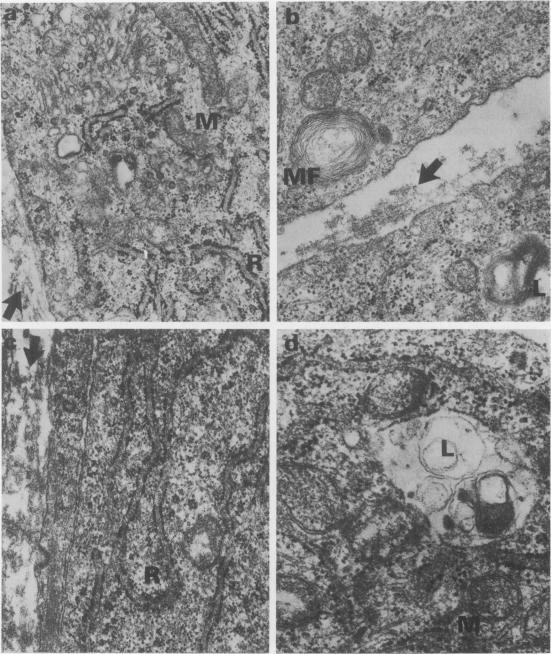

The cell layers and medium of cultured porcine and bovine aortic endothelium have been examined to test the effects of 24 h treatment with two factors associated with cigarette smoke--hypoxia and carbon monoxide, on cell numbers, total protein including collagen/10(6) cells, collagen type profile and ultrastructure. The most significant findings were that the responses varied with the species and that the effects on protein synthesis including collagen differed depending on the nature of the insult; in general, moreover carbon monoxide tended to reverse the action of hypoxia, a finding supported by ultrastructural evidence. The phenotypic collagen profiles were unaffected by either hypoxia or carbon monoxide.

已对培养的猪和牛主动脉内皮细胞层及培养基进行了检测,以测试与香烟烟雾相关的两个因素——缺氧和一氧化碳,对细胞数量、包括胶原蛋白在内的每10⁶个细胞的总蛋白量、胶原蛋白类型谱以及超微结构进行24小时处理后的影响。最显著的发现是,反应因物种而异,并且对包括胶原蛋白在内的蛋白质合成的影响因损伤性质不同而有所差异;此外,一般而言,一氧化碳倾向于逆转缺氧的作用,这一发现得到了超微结构证据的支持。缺氧和一氧化碳均未影响表型胶原蛋白谱。